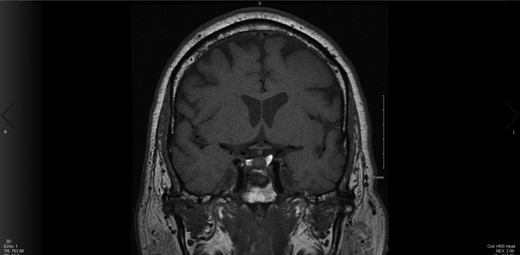

Upon the unimpressive decrease in HbA1C despite an appropriate increase in medical therapy, Cushing’s syndrome was suspected and diagnostic work up was pursued (Fig. 1). A dexamethasone suppression test as well as a late night salivary cortisol test showed abnormal results. The late night cortisol test showed high values congruent with the range necessary for diagnosis of Cushing’s syndrome (>7.5 mcg/dl) [3]. These findings were suggestive of ACTH-dependent Cushing’s syndrome. At this point, an MRI of the brain with sella protocol was ordered and showed no evidence of a pituitary adenoma or pituitary etiology (Fig. 2). Bilateral inferior petrosal sinus sampling was performed (IPSS) and the results were highly suspicious for pituitary microadenoma located more on the left side of the gland, with some activity also present on the right side (Fig. 3). The peak IPSS ACTH value was 1031 pg/ml. A repeat MRI of the brain with sella protocol with higher resolution (3 T MRI with sella protocol with thin cuts) was done in order to visualize the lesion for surgical planning, which did not show any pituitary lesion. FSH, LH, prolactin, insulin-like GF-1, TSH, free T4 and testosterone labs were ordered, and all were within normal limits.

Testing to establish the cause of Cushing’s syndrome Reproduced with permission from: Nieman LK. Establishing the cause of Cushing’s syndrome. In: UpToDate, Post TW (Ed), UpToDate, Waltham, MA. (Accessed on [Date].) Copyright © 2019 UpToDate, Inc. For more information visit www.uptodate.com.